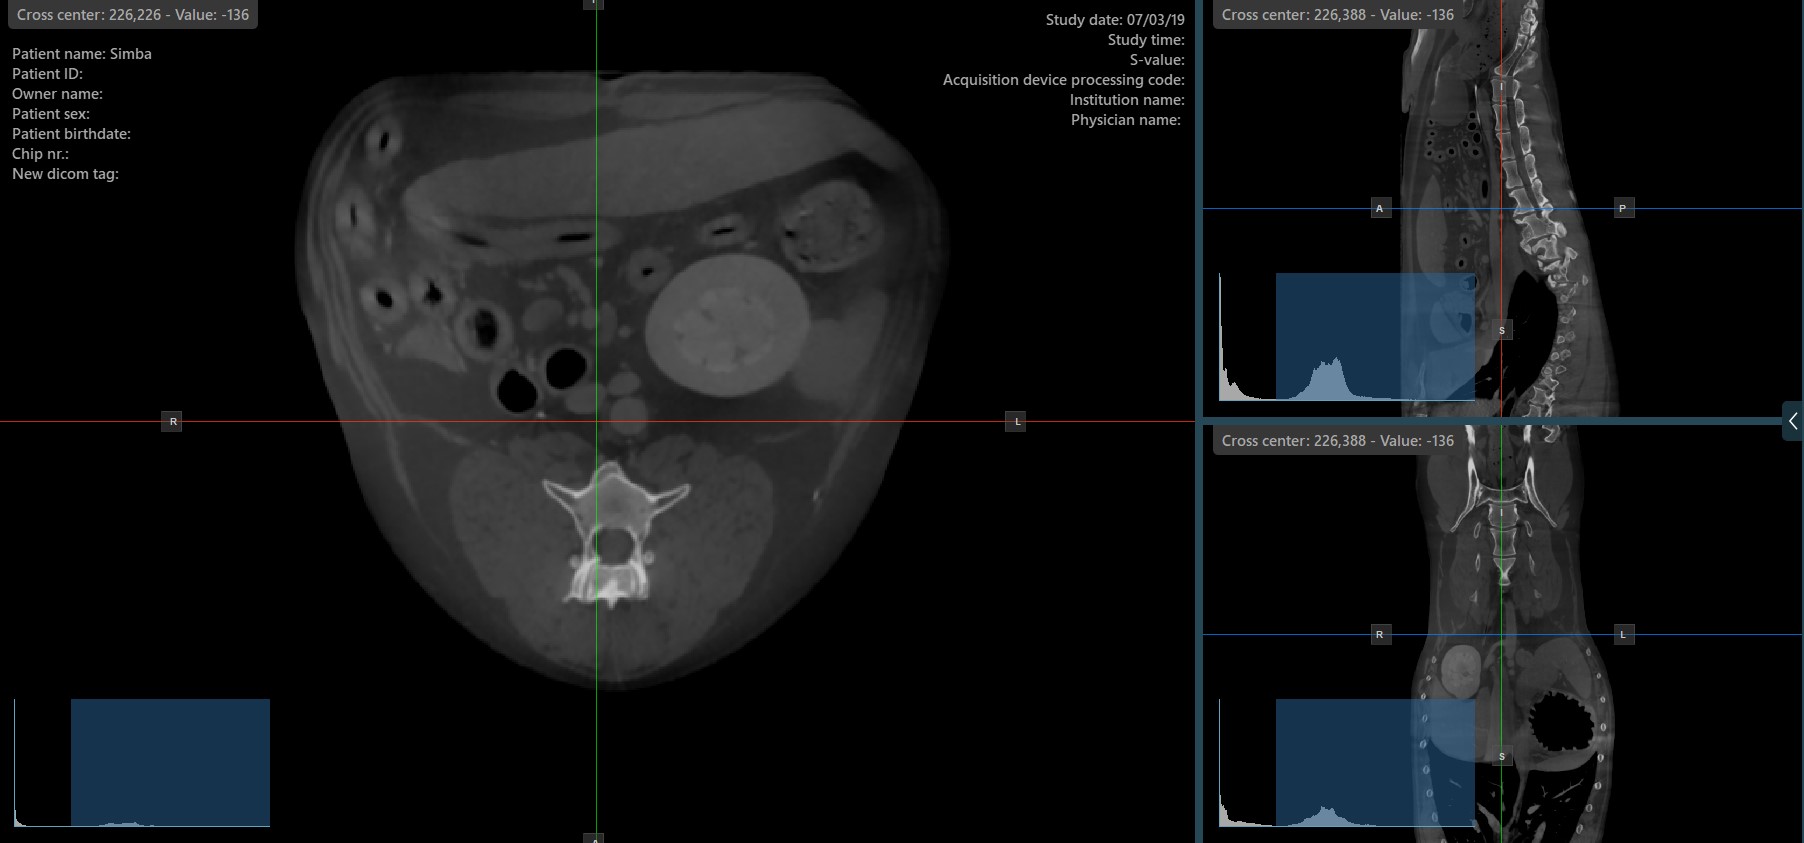

Press the Perpendicular Slicers icon in the left toolbar to activate simultaneous rotation of the slicers. Regardless of their previous orientation, the slicers are repositioned to be perpendicular to each other.

Toggle the Perpendicular Slicers option to switch the active mode of the slicers at any time, or choose one of the Tools -> Perpendicular Slicers or Tools -> Separate Slicers options from the CT Viewer menu.